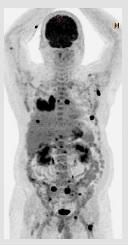

正子電腦斷層掃描(PET-CT)是將正子掃描儀與電腦斷層掃描儀結合在一起,進行全身腫瘤偵測的檢查。目前最常用的PET-CT放射藥物為F-18 FDG (氟18去氧葡萄糖)。F-18 FDG是一個與葡萄糖非常相似的分子,可用於評估病人體內組織器官對葡萄糖代謝的狀況。而通常腫瘤細胞之新陳代謝比較旺盛,亦會吸收較多的葡萄糖,所以PET-CT得以偵測病人體內的肺癌細胞,進而提供肺癌分期、復發時再分期、及治療效果的評估。

正子掃描發現右下肺癌外,身上多處淋巴結及骨轉移病灶。

不過,有時肺癌細胞型態的不同或體積太小,仍有可能偵測不到癌細胞;而有時身體有感染或發炎,感染或發炎部位也會吸收F-18 FDG,因此掃描結果仍需經由臨床或病理診斷來佐證。